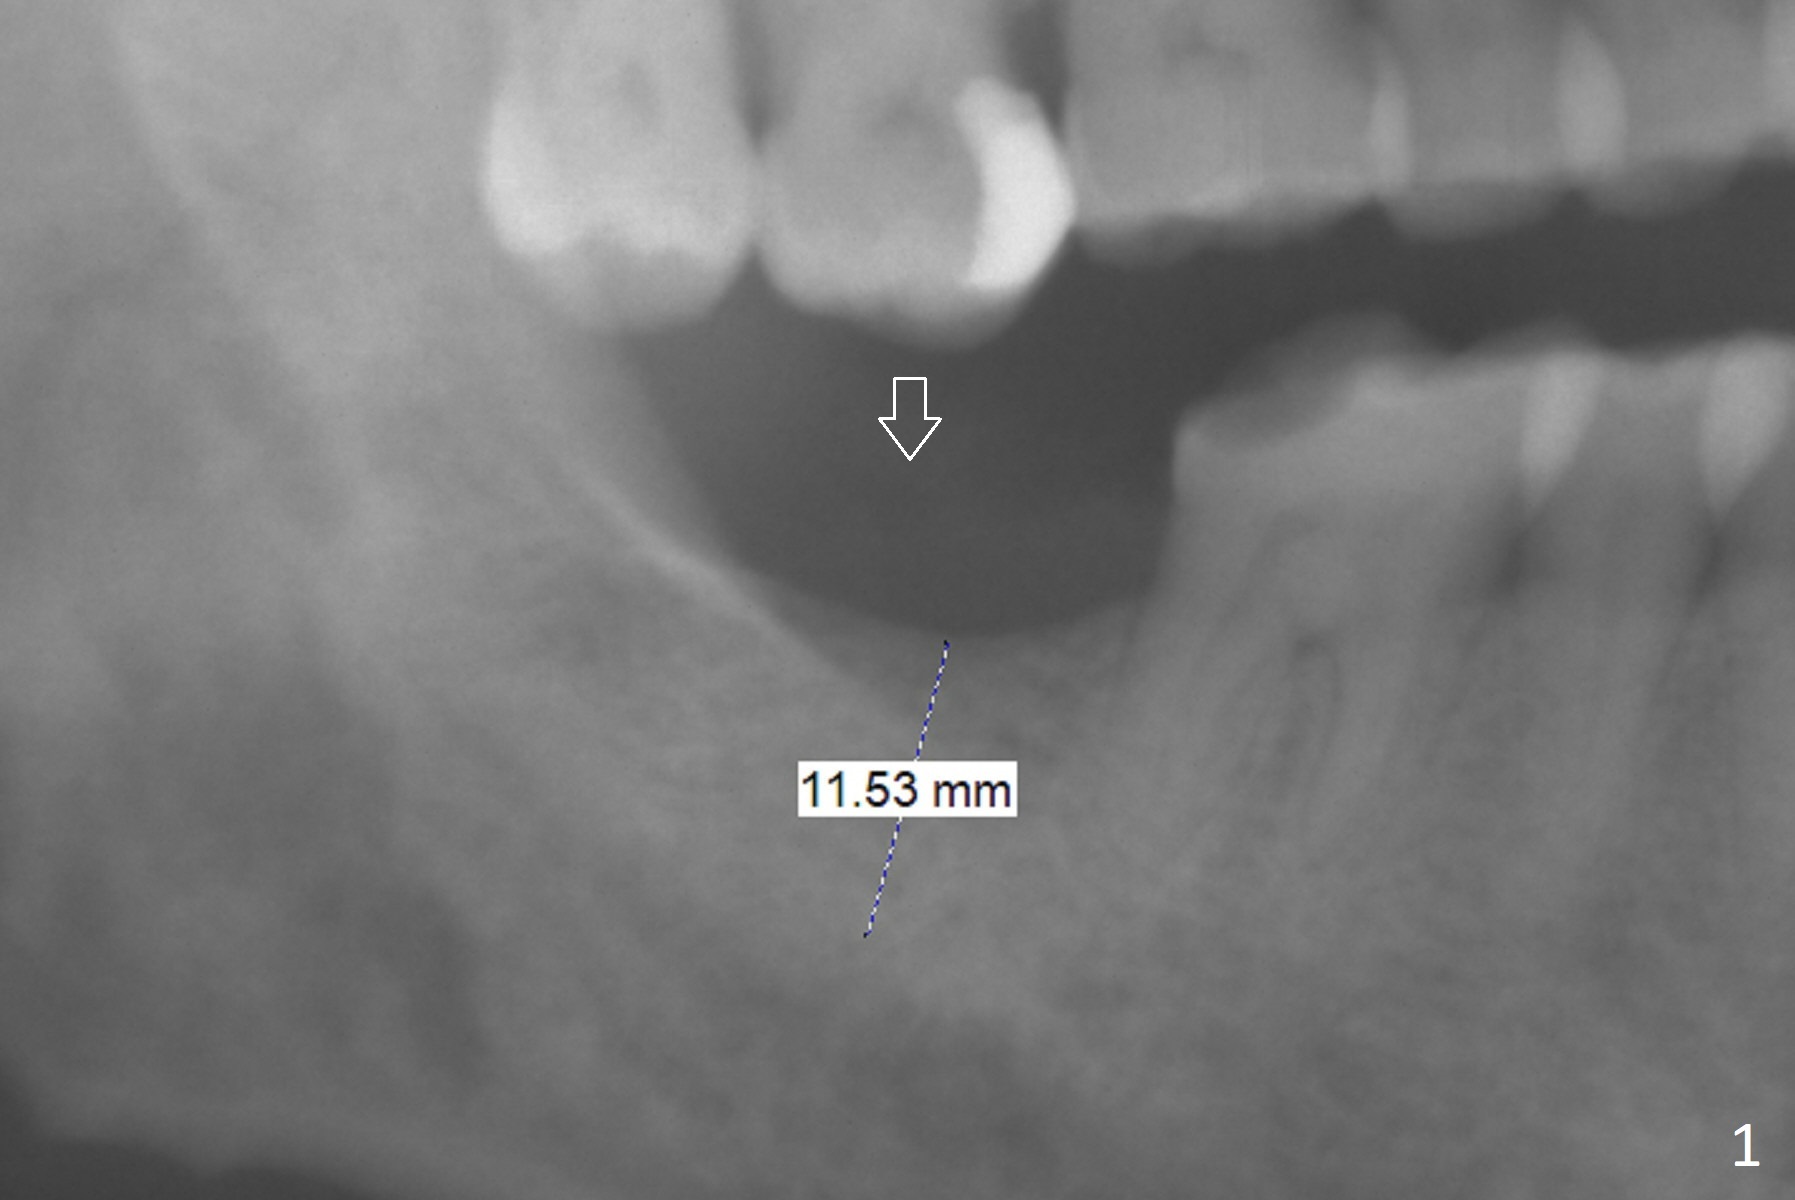

Supraeruption

A 59-year-old man will return for #31 implant placement 2 months after #15 one (Fig.1). Since the opposing tooth is supraerupted (arrow), the depth of osteotomy will be 11.5 mm, while an implant will be 10 mm long. Immediately (probably 2 weeks) after the surgery, two mini-implants will be placed for orthodontic intrusion.